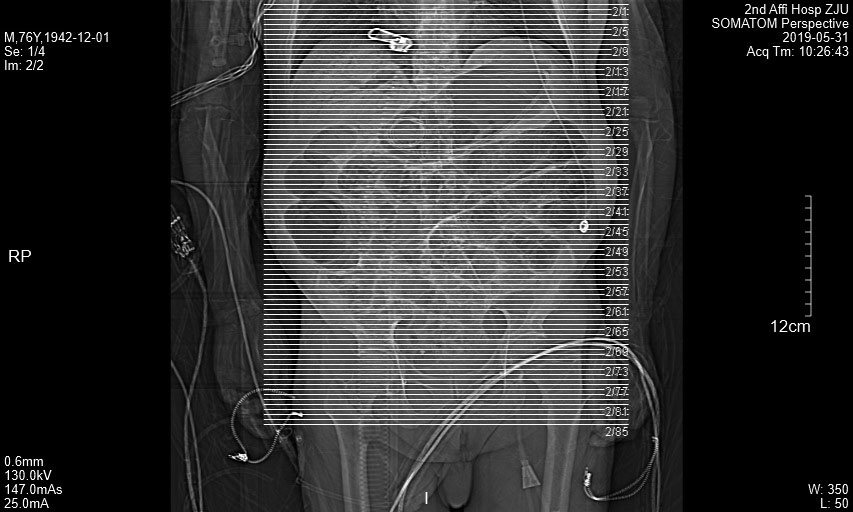

附图2 患者冠状面CT图